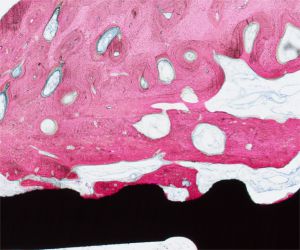

硬组织切片病理服务